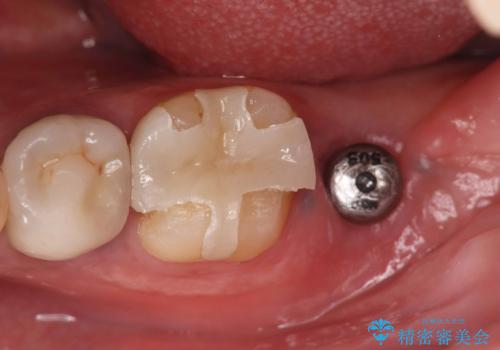

- 過去にヘミセクションが行われていたと思われる左下7番は、大きな歯根嚢胞および根尖病変が認められ、さらに骨縁下カリエスを伴っており、歯肉には瘻孔が形成されている状態でした。

保存は困難と判断し、左下7番は抜歯即時インプラントによる治療を行いました。

また、左下6番には形態が不自然で適合不良のセラミックインレーが装着されていたため、二次カリエスのリスクを考慮し、オールセラミッククラウンによる治療を行いました。

抜歯と同時にインプラントを埋入するため、歯茎を切開する必要がなく、術後の痛みが出にくい治療方法です。